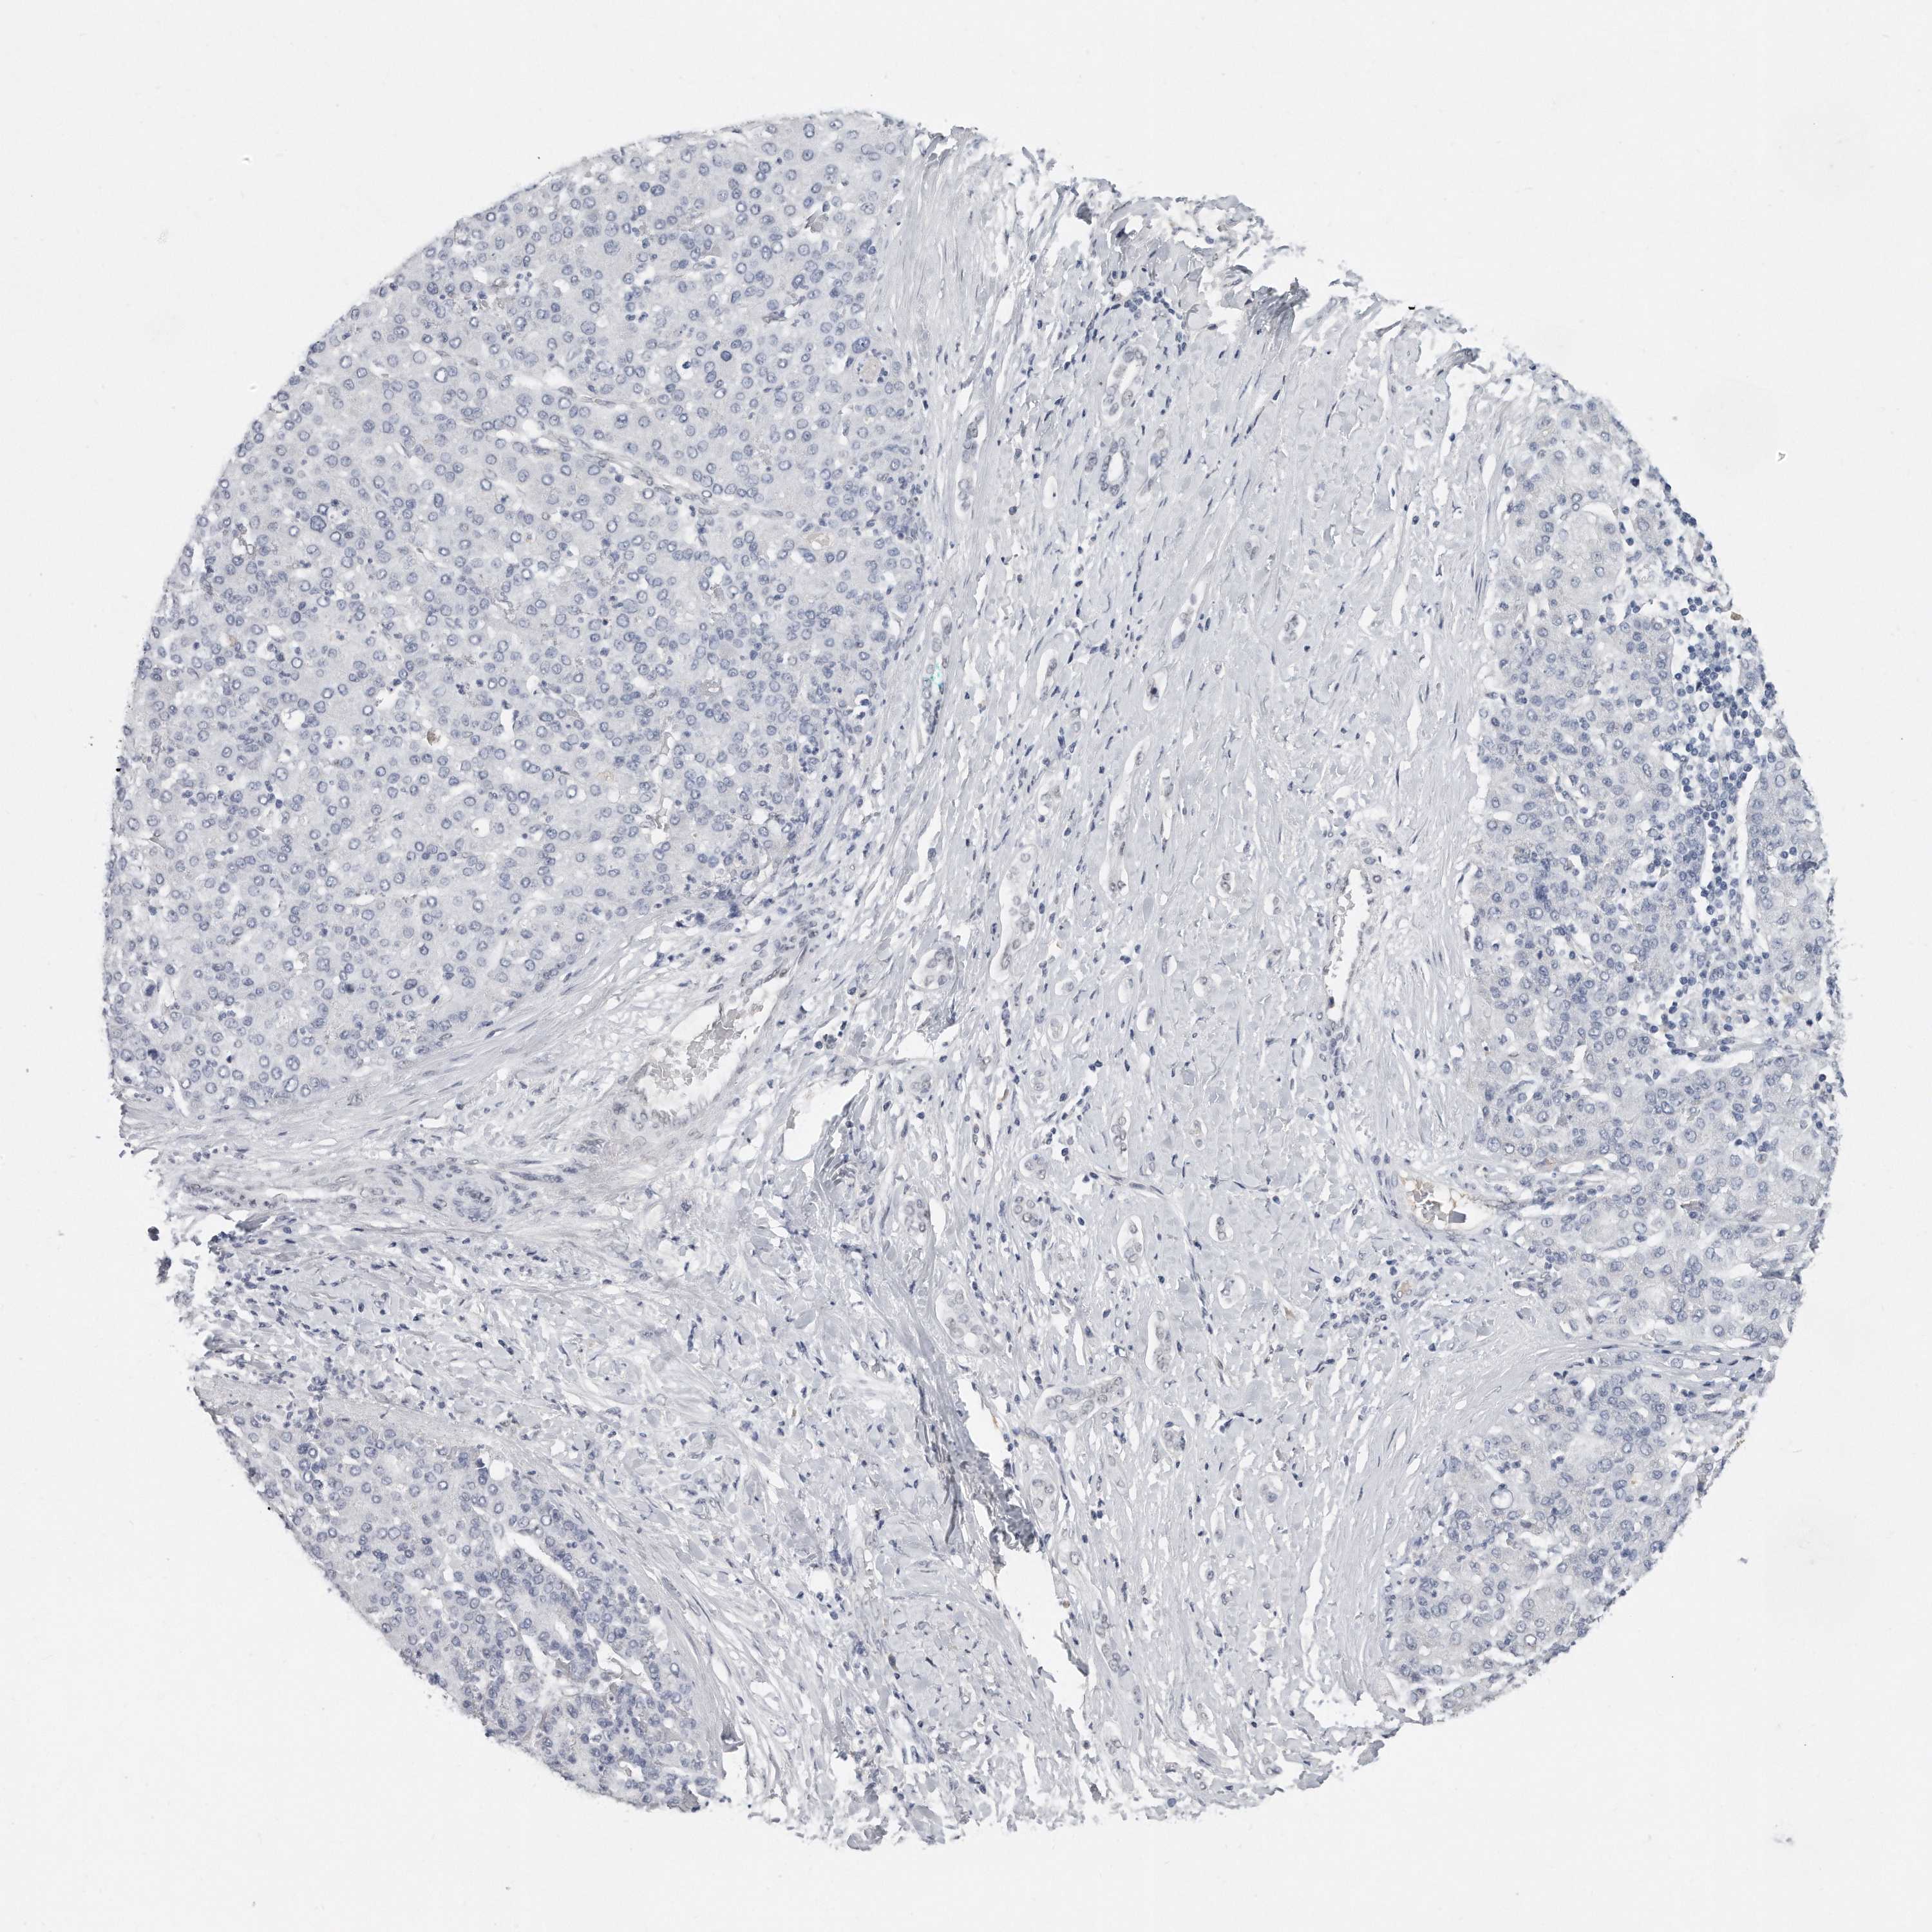

LIVER CANCER - Protein expressioni

A mouse-over function shows sample information and annotation data. Click on an image to view it in a full screen mode. Samples can be filtered based on level of antibody staining by selecting one or several of the following categories: high, medium, low and not detected. The assay and annotation is described here.

Note that samples used for immunohistochemistry by the Human Protein Atlas do not correspond to samples in the TCGA dataset.

Antibody stainingi

Antibody staining in the annotated cell types in the current human tissue is reported as not detected, low, medium, or high, based on conventional immunohistochemistry profiling in selected tissues. This score is based on the combination of the staining intensity and fraction of stained cells.

Each image is clickable and will lead to virtual microscopy that enables deeper exploration of all samples and also displays staining intensity scores, fraction scores and subcellular localization as well as patient and tissue information for each sample.

Antibody HPA023559

Antibody HPA023564

Antibody HPA044971

Antibody CAB031916

Staining

High

Medium

Low

Not detected

Intensity

Strong

Moderate

Weak

Negative

Quantity

>75%

75%-25%

<25%

None

Location

Nuclear

Cytoplasmic/membranous

Cytoplasmic/membranous,nuclear

Cholangiocarcinoma

Carcinoma, Hepatocellular, NOS